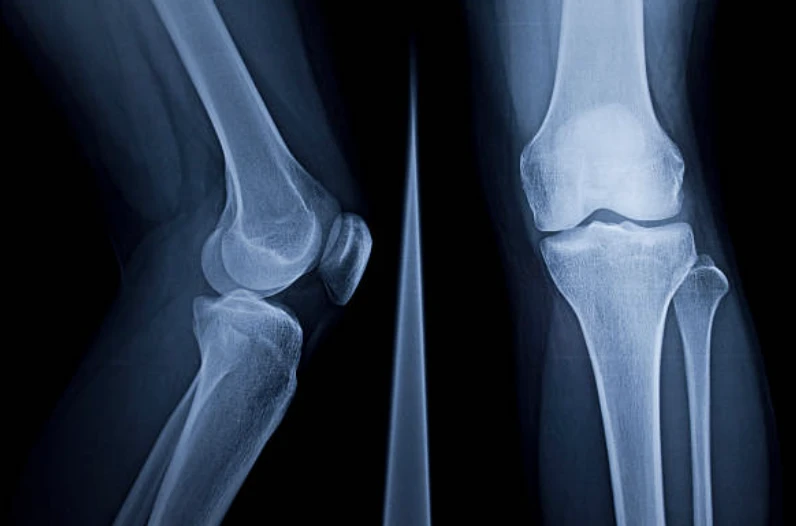

- 무릎 부상에 대해서 병원 진료를 받을 때는 일반적으로 X-레이, MRI, CT 스캔 또는 관절경과 같은 진단 절차가 진행될 수 있습니다.

무릎 통증에 대한 병원 진료

- 엑스레이(X-ray) : 눈에 보이지 않는 전자기 에너지 빔을 사용하여 내부 조직과 뼈 및 장기에 대한 사진을 필름에 만듭니다.

- MRI : 대형 자석, 무선 주파수 및 컴퓨터를 사용하여 신체 내 장기 및 구조를 상세하게 이미지화 합니다. 주변 인대나 근육 손상도 확인할 수 있습니다.

- CT 스캔 : X-ray 기술을 사용하여 신체의 수평 또는 축 이미지를 만들어 냅니다. CT 스캔은 뼈, 근육, 지방 및 장기를 포함한 신체의 모든 부분에 대해 상세히 이미지화합니다.

- 방사선핵종스캔 : 미량의 방사성 물질을 사용하는 핵 영상 기술로 환자의 혈류에 주입하여 스캐너로 감지합니다. 이 검사를 통해 혈류와 뼈 내 세포 활동을 확인할 수 있습니다.